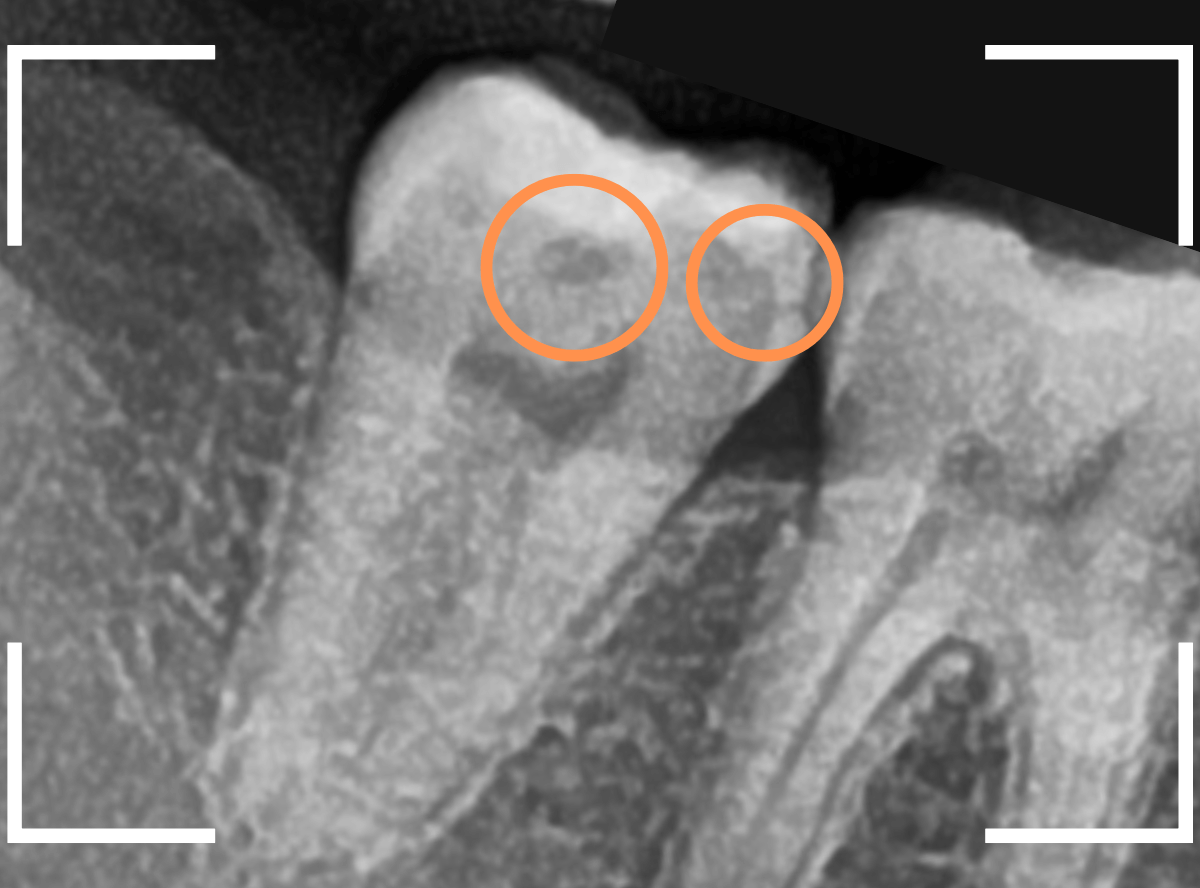

Case.17 レントゲンにはっきり写らないレジンの中の虫歯を削って調べる2

今回も、下の奥歯の虫歯を治療した例です。

特に症状はありませんが、以前に治療したレジンが劣化してすり減っているのと、少し中が黒く透けて見えて、虫歯になっているのが怪しいです。

青いラインが歯の神経です。

以前の虫歯が深めだったようで、レジンが深めにつめてあるのがわかります。

その下がうっすらと虫歯っぽい影になっています(赤いライン)。

虫歯になっているか微妙なラインですが、レジンも劣化していますので、患者さんにご説明して治療することになりました。